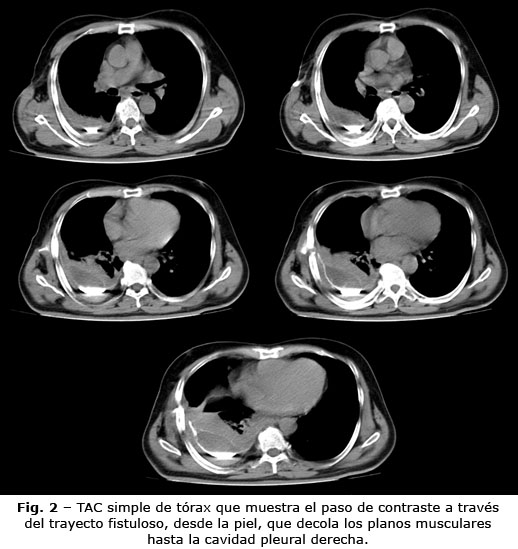

La tomografía axial computarizada (TAC) simple de tórax muestra colección líquida pleural densa 30-37 unidades Hounsfield (UH) y encapsulada en hemitórax derecho, de mediana cuantía sugestiva de empiema, así como paso de contraste a través del trayecto sinuoso desde la piel, que decola planos musculares hasta la cavidad pleural ipsilateral en relación con la fístula pleurocutánea (Fig. 2). En el resto del estudio no se evidenciaron alteraciones nodulares ni inflamatorias del parénquima pulmonar. No había adenopatías mediastínicas ni alteraciones óseas degenerativas.